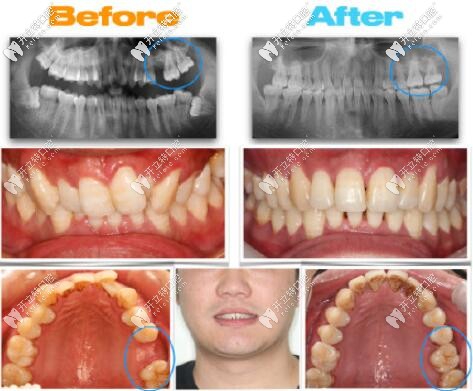

大牙缺失通過正畸,智齒前移代替磨牙的成功案例分享

智齒發(fā)布時(shí)間: 2025-05-13

牙齒缺失沒有種牙,求齒前移代替大牙的案例,那么智齒前移當(dāng)磨牙的條件是什么?